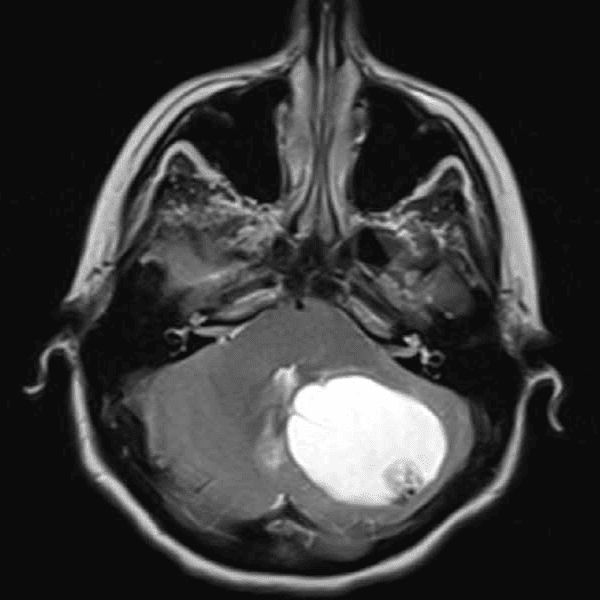

Classic Cases